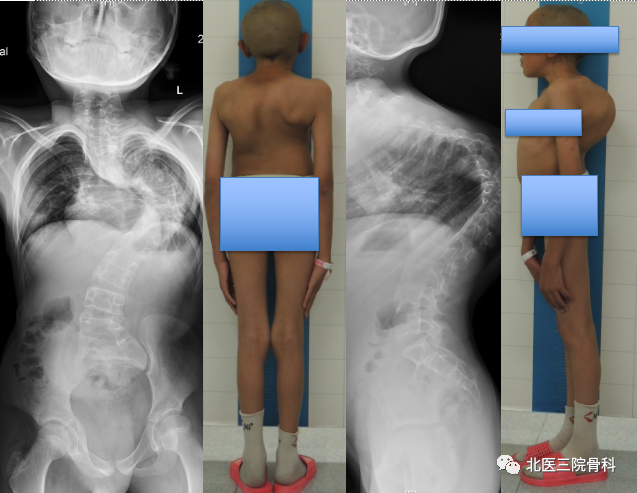

先天性脊柱侧后凸畸形大体照及影像学

(术前)

(术后)